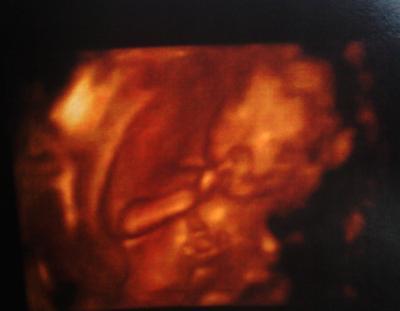

Huhu, bin auch zurück vom FA. Also nun sind wir 100% sicher das es ein Junge wird Dem kleinen geht es super, er ist gut entwickelt wiegt 202gramm und er wird gut von mir versorgt. Beim nächsten mal schaut er sich die Organe genauer an. Ich habe nochmal 2 Kilo zugenommen, bin jetzt bei 5,5 Kilo. Mein FA hat gesagt das ich mich gesünder ernähren soll. Ist zwar noch alles im rahmen,aber sonst habe ich am schluss +18 Kilo oder so. Er hat mir ein 4D Bild geschenkt, ich hänge es mal dran. Ach so, über einen Namen sind wir uns nicht einig. Ich finde Kilian schön, mein Freund möchte einen amerikanischen Namen (er hat mal in Amerika gelebt). Liebe Grüße Kathrin

Bild zu Zurück vom FA mit 4D Bild - Forum für März - Mamis

Juhu, schön, dass bei euch alles ok ist. Das freut mich sehr. Süßes Bildchen hast du da bekommen. Weiß dein Freund denn schon, was für einen Namen er sich vorstellt? Hab weiter unten ja einen Link reingestellt. Da gibt es auch tolle besondere Namen. LG Claudia

der ist ja süß. das sieht aus als hätte der den finger in der nase. nächste woche habe ich auch endlich wieder termin. lg

Der 4D-Ultraschall ist im Prinzip ein 3D-Ultraschall, bei dem jedoch als vierte Dimension der Faktor Zeit miteinbezogen wird. Dies bedeutet also eine dreidimensionale Darstellung des Kindes unter Echtzeitbedingungen. Aus diesem Grund wird die 4D- Ultraschalluntersuchung auch als Live 3D-Ultraschall bezeichnet.